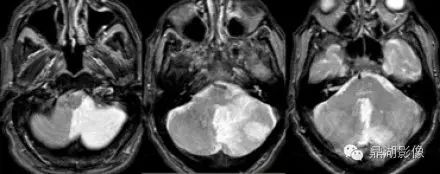

小脑后下动脉梗塞

049407cca69df20d05fdb709694f623a.gif

小脑上动脉梗塞

65fad851087608397671532d353a4d7b.jpg